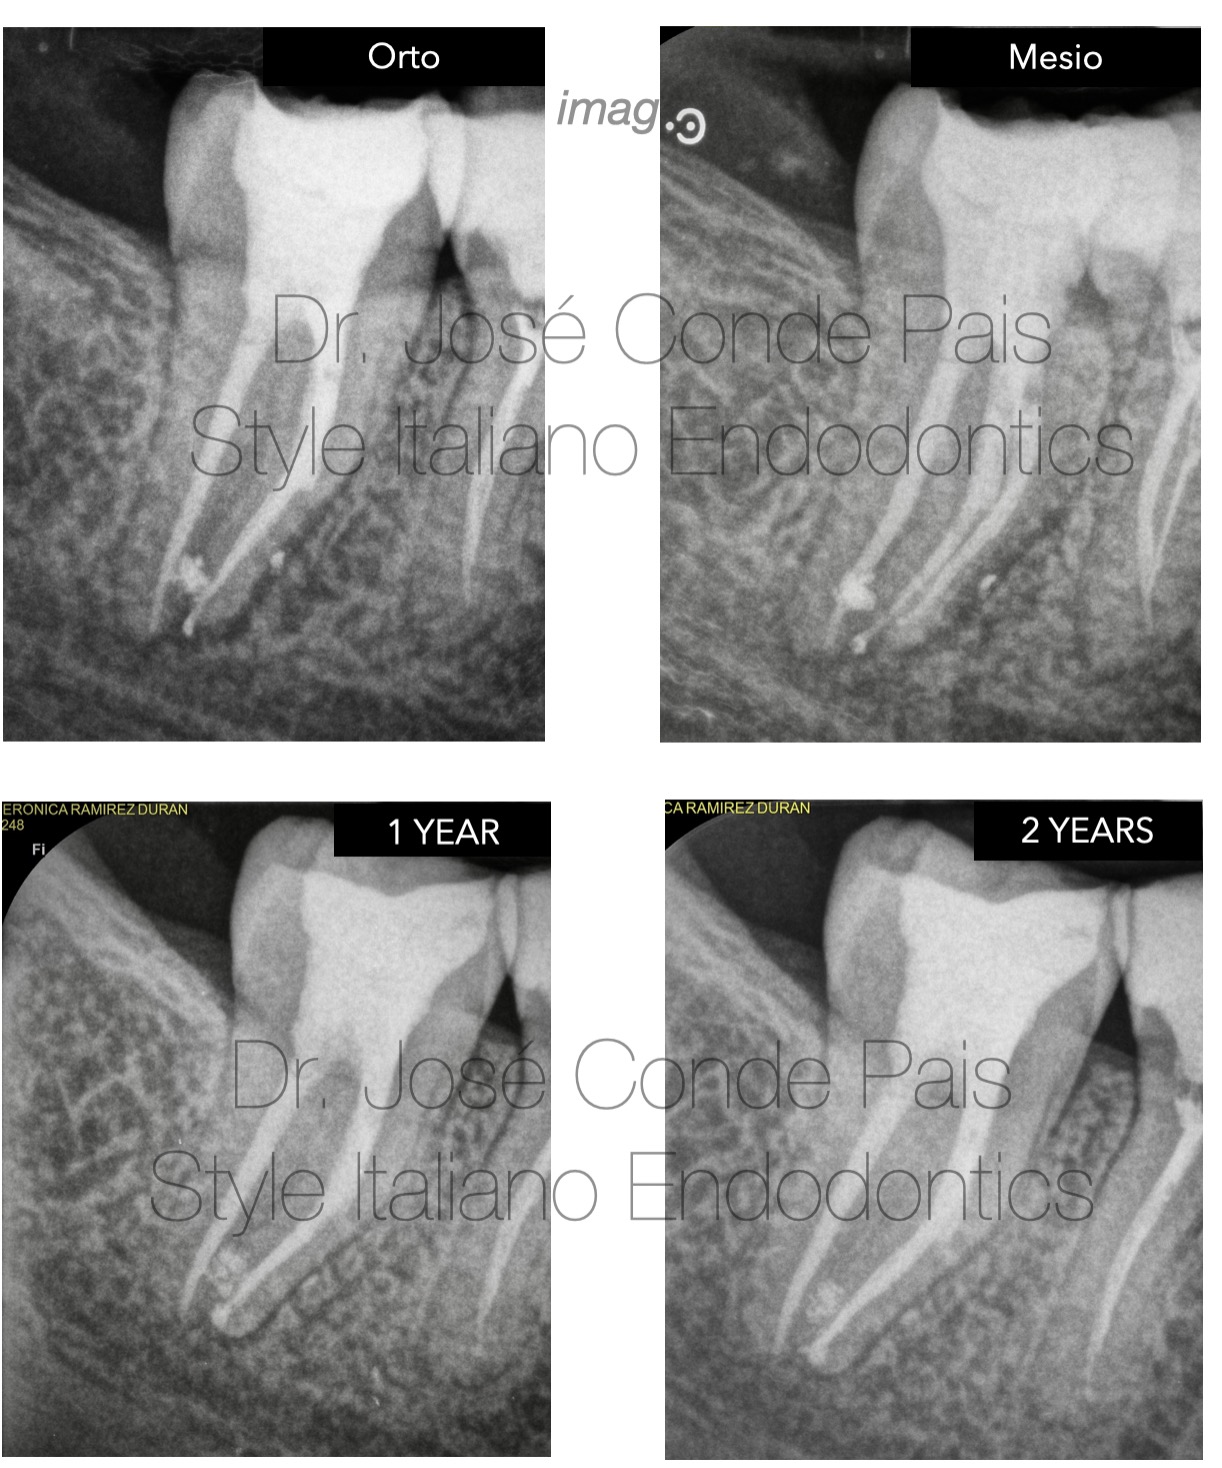

Fig. 6

Healing dynamics and 2 years outcome

Following successful orthograde retrieval, the case was completed with three-dimensional cleaning and obturation of the root canal system.

The immediate postoperative radiograph shows an adequate obturation, respecting the original anatomy.

An angled radiograph was also taken to better assess the complexity of the mesial root system and confirm the quality of the treatment.

At the 1-year follow-up, a clear reduction in the periapical radiolucency can be observed, indicating favourable healing.

At 2 years, complete radiographic resolution of the lesion is evident, confirming long-term success.